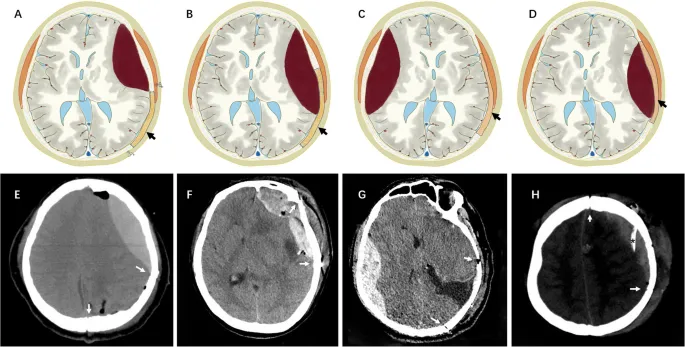

- Evacuation of space-occupying hematomas (epidural, subdural).

- Decompressive craniectomy for refractory intracranial pressure (↑ICP).

- Hemorrhage (EDH, SDH, IPH): Presents with new focal deficits or ↓LOC. Requires urgent CT scan.